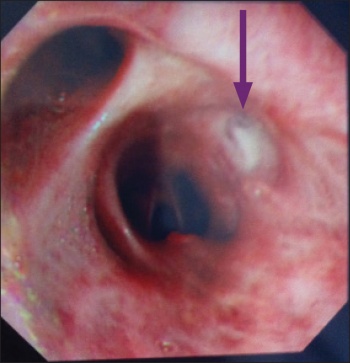

Figure 3. Initial bronchoscopy that revealed lesion (arrowed) which was shown to be incidental finding with a benign histology

Figure 3. Initial bronchoscopy that revealed lesion (arrowed) which was shown to be incidental finding with a benign histology(click to enlarge)

Bronchoscopy showed incidental finding of a mass-like lesion at the right bronchus intermedius (see Figure 3), which wasn’t picked up on in the CT.

The biopsy from that lesion came back as a benign inflammatory growth with no feature suggestive of primary or secondary neoplasm and it is very unlikely to have such a clinical impact on the patient’s condition. Bronchial washings were negative.